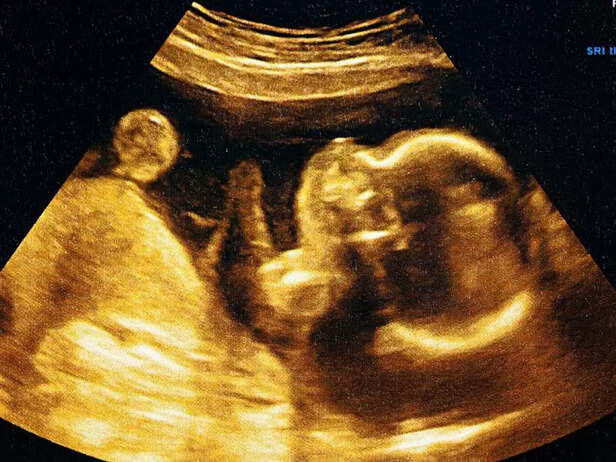

2. Formation of Facial Features

BABY SONOGRAPH

During week 6, the early formation of your baby's facial features becomes evident, even though they are still in their early stages.

a. Eyes:

The baby's eye structures begin to form, with dark spots appearing where the eyes will eventually be. Initially, the eyes are on the side of the head at the start, but they will slowly move to the front as the face takes shape.

b. Nose:

The formation of the baby's nose is also on the way now, starting as two small dents in the nasal region.Over time, these dents will develop to form the characteristic shape of a human nose

c. Mouth and Lips:

During this phase, your baby's mouth and lips are also taking shape,, with small dents forming showing where the mouth and upper lip will be.

d. Ear Buds:

By the end of week 6, ear buds, which will develop into the baby's ears, are also becoming visible on the sides of the head.